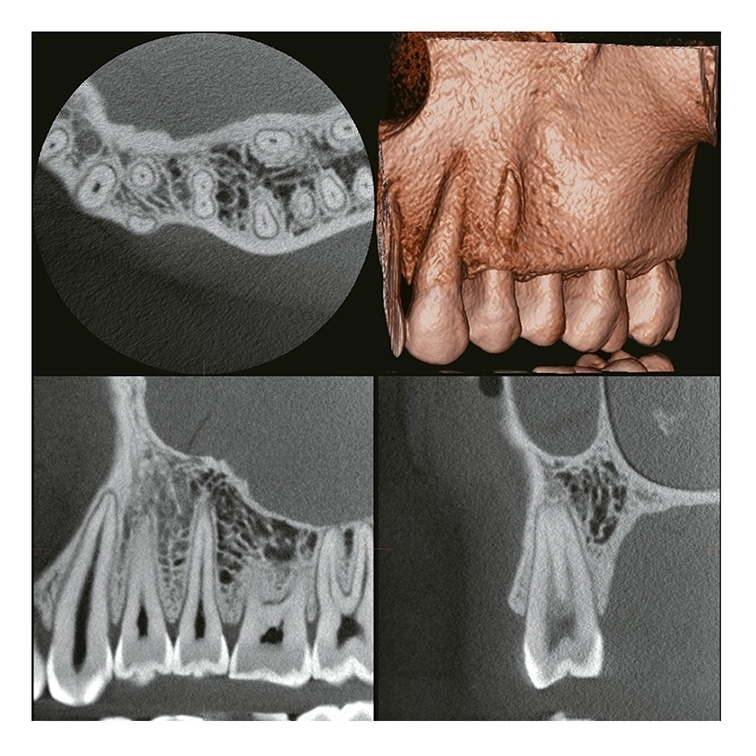

2 VERAVIEW (X800) CP (S) / (M) / (L)

Panoramique/Céphalostat 3D & 2D

FOV Jusqu'à: Ø 150 X H 140